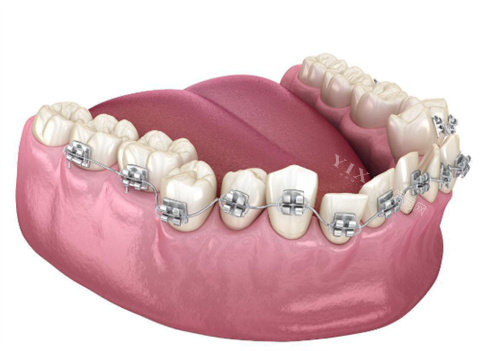

牙齿矫正旨在改善牙齿排列不齐、咬合异常等问题,提升口腔健康和美观度。三沙地区的牙齿矫正价格因矫正方式、材料和医院等级的不同而有所差异。

金属托槽矫正器:价格相对较为亲民,适合大多数青少年和成人。价格区间大约在5000元至15000元不等。

陶瓷托槽矫正器:陶瓷托槽矫正器美观度较高,适合希望保持外观美观的成年人。价格区间大约在8000元至20000元不等。

隐形矫正器:隐形矫正器舒适度好,可自行摘戴,不影响日常生活和饮食,美观度高。价格范围广泛,从15000元至45000元不等。出名品牌如隐适美、时代天使等,价格区间较大,例如美国隐适美隐形矫正的价格约为42000元起,时代天使隐形矫正的价格约为40000元起。